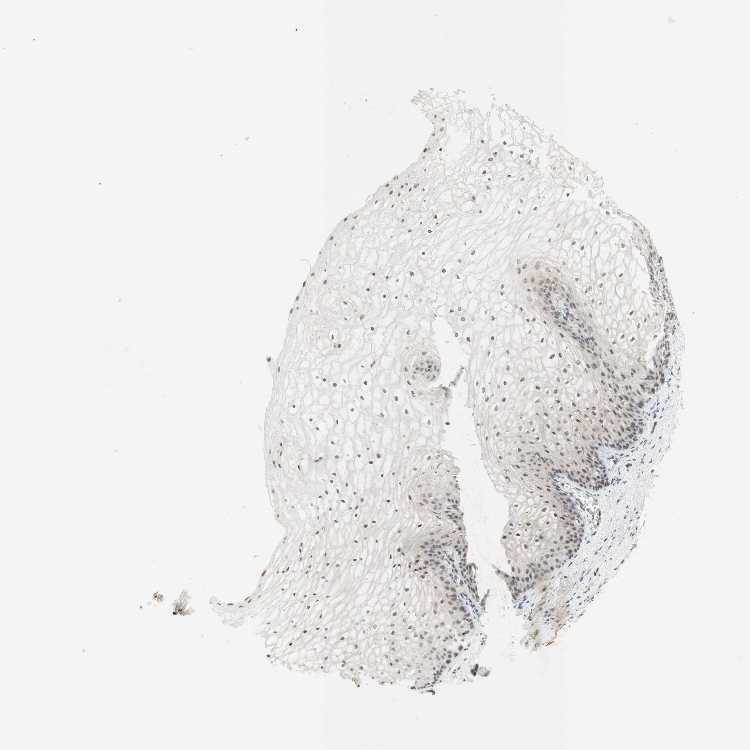

VAGINA - Antibody stainingi

Antibody staining in the annotated cell types in the current human tissue is reported as not detected, low, medium, or high, based on conventional immunohistochemistry profiling in selected tissues. This score is based on the combination of the staining intensity and fraction of stained cells.

Each image is clickable and will lead to virtual microscopy that enables deeper exploration of all samples and also displays staining intensity scores, fraction scores and subcellular localization as well as patient and tissue information for each sample.

Antibody HPA063131Antibody CAB011662

Squamous epithelial cells Not detectedMedium